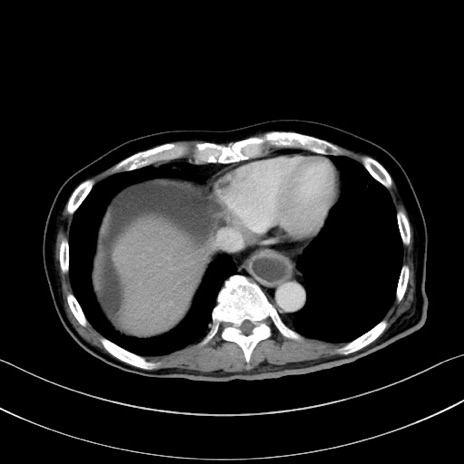

症例28(横断像)

【症例】60歳代男性

【現病歴】胃癌にて胃全摘後。食思不振が悪化し、夜中に嘔吐することがある。

【既往歴】胃癌、胃全摘、脾摘、胆摘後